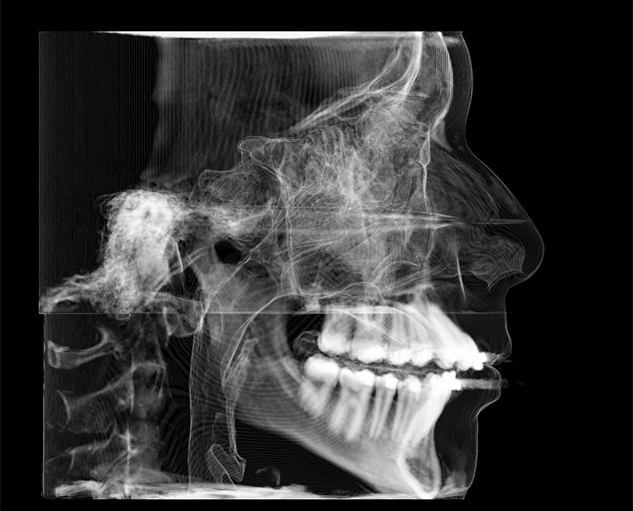

Teleradiology is an internet based radiology system wherein captured images from sources like X-Ray, CT Scan, CBCT Scan, MRI etc are sent to another location via web,so that an expert radiologist at another location can read the images for the purpose of generating reports and image portfolios.

About Us

Welcome to ScanReadrz

Administered by the team of experienced radiologists who are established in the field of Maxillofacial Radiology and managing multiple radiology centres in different states of India.

Having faced the challenges of Maxillofacial Radiology in small and large cities alike, we completely understand the needs and expectations of clinicians and diagnostic centres..

Why ScanReadrz?

On every case submitted, we ask you to identify the clinical purpose(s). ScanReadrz has developed specific diagnostic objectives for each clinical purpose that will be addressed by the radiologist. This ensures that the report is relevant to your diagnosis and treatment planning.